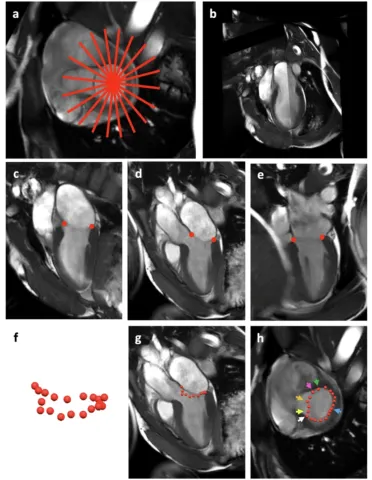

An axis-specific mitral annuloplasty ring eliminates mitral regurgitation allowing mitral annular motion in an ovine model